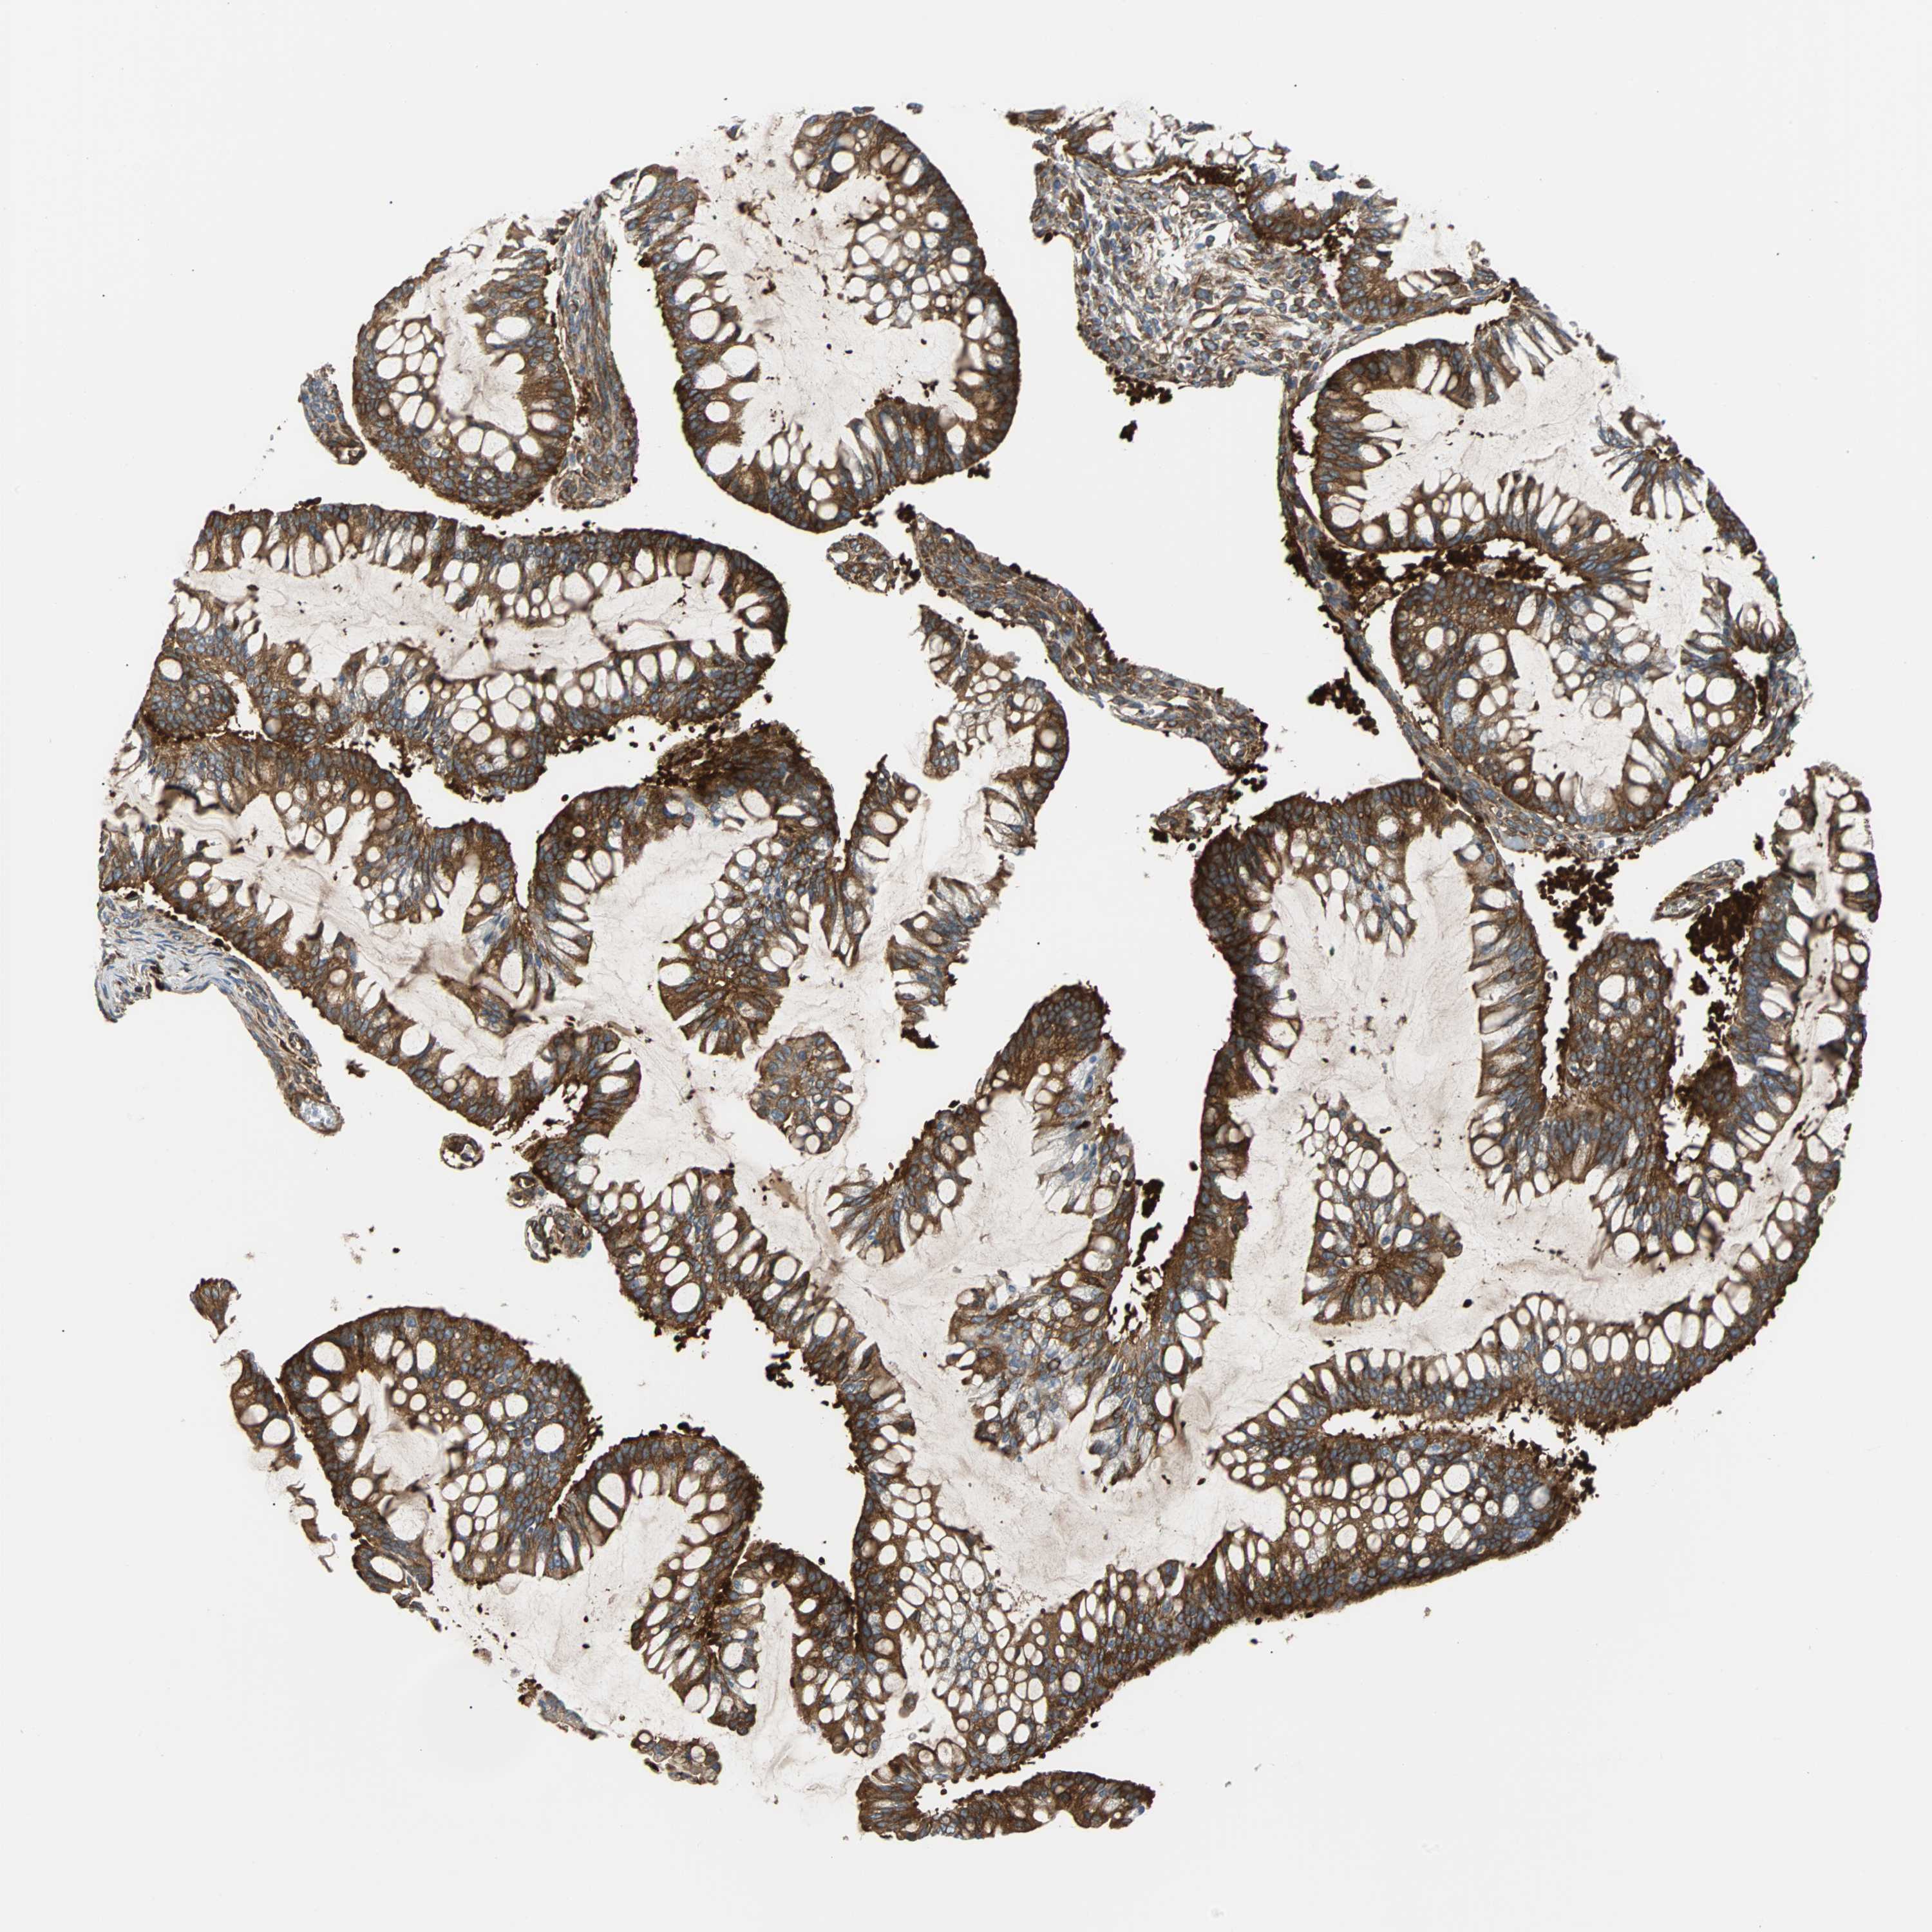

OVARIAN CANCER - Protein expressioni

A mouse-over function shows sample information and annotation data. Click on an image to view it in a full screen mode. Samples can be filtered based on level of antibody staining by selecting one or several of the following categories: high, medium, low and not detected. The assay and annotation is described here.

Note that samples used for immunohistochemistry by the Human Protein Atlas do not correspond to samples in the TCGA dataset.

Antibody stainingi

Antibody staining in the annotated cell types in the current human tissue is reported as not detected, low, medium, or high, based on conventional immunohistochemistry profiling in selected tissues. This score is based on the combination of the staining intensity and fraction of stained cells.

Each image is clickable and will lead to virtual microscopy that enables deeper exploration of all samples and also displays staining intensity scores, fraction scores and subcellular localization as well as patient and tissue information for each sample.

Antibody CAB004264

Antibody CAB005030

Staining

High

Cystadenocarcinoma, serous, NOS

Carcinoma, endometroid

Carcinoma, NOS

Cystadenocarcinoma, mucinous, NOS